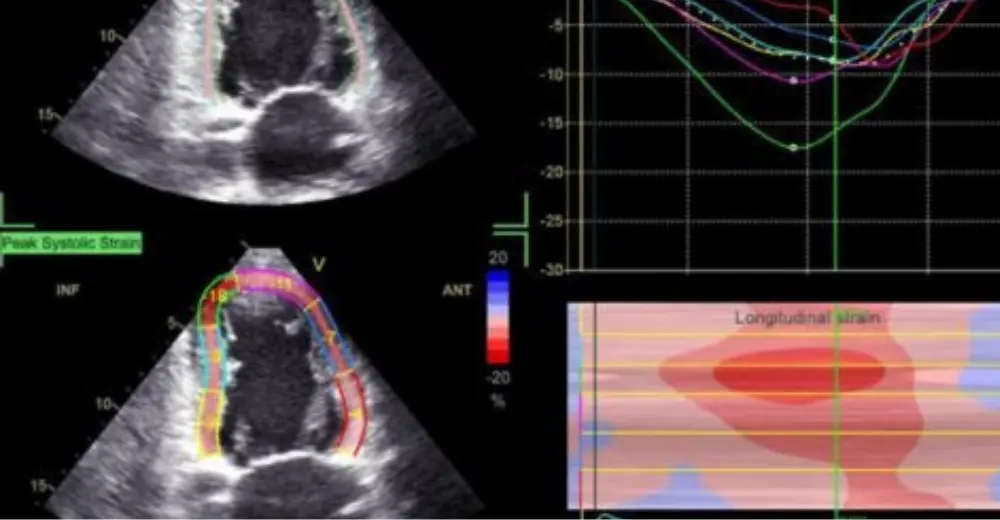

Це сучасна методика ехокардіографії (ЕхоКГ), заснована на аналізі руху спеклів (акустичних точок або плям), отриманих в 2D (двовимірному) режимі. Найчастіше оцінюється деформація (стрейн) міокарда у трьох площинах: повздовжній (longitudinal), радіальній (radial) та циркулярній (circumflex).

📈 Яким чином подається результат?

Найчастіше оцінюється глобальний повздовжній стрейн (GLS) лівого шлуночка. Математично оброблений результат подається у вигляді 16- або 17-сегментної діаграми (bull`s eye), графіків та значень GLS, отриманих з трьох різних зрізів (LAX, A2Ch, A4 Ch) та середнє значення GLS